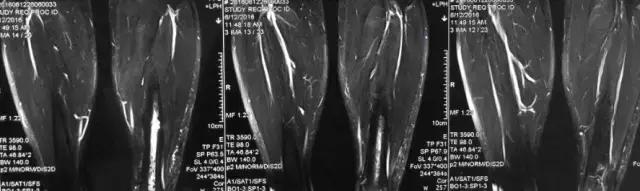

影像检查

诊断:感染。 检查:膝关节MRI,确认伤口窦道是否与髓腔相通。 治疗:1、血沉和C反应蛋白正常,目前无需特殊处理。 2、如果窦道反复出现或血沉和C反应蛋白升高可考虑手术。如证明窦道与髓腔相通,需行扩髓。

核磁示中下段骨髓炎,上面切口处流脓,请问张主任你的意见要上手术吗?